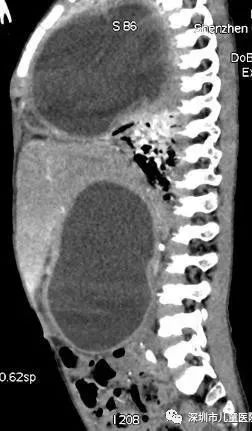

手术前,京京胸腹部CT侧面,两处黑色包块状阴影分别为胸腔、腹腔囊肿。

检查结果,让医生倒吸了一口凉气——

京京右侧胸腔及右侧腹腔,

各有一个巨型囊肿。

这就像,在他的肚子里塞进了两个“大气球”。正是由于“气球”压迫了肺部,他才会呼吸困难,随时都会有生命危险。